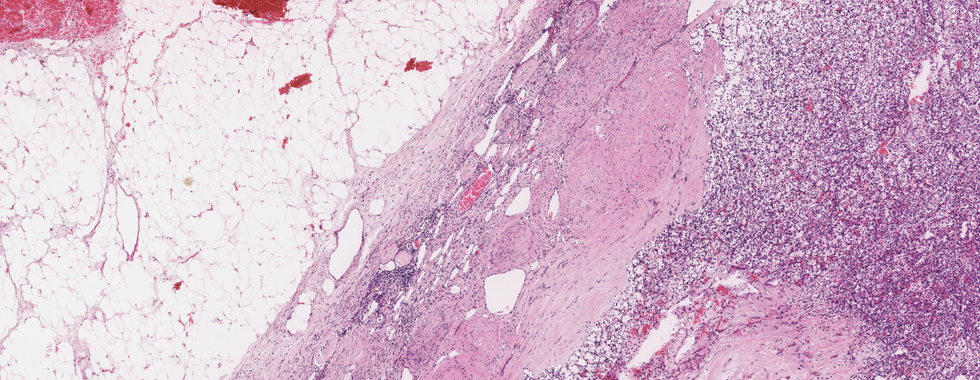

Scroll down to see final diagnosis and case discussionDiagnosis: Clear cell renal cell carcinoma

Microscopic Pathology

· Predominantly solid tumour pattern with alveolar and acinar tumour cell arrangement separated by a characteristicvascular stroma showing prominent network of small, thin-walled blood vessels.

· Other patterns noted, include trabecular, microcystic, and pseudopapillary, tubular in rare cases. Sarcomatoid differentiation with spindle cell formation can be seen.

· Individual tumor cells are large with optically clear to deeply granular cytoplasm.